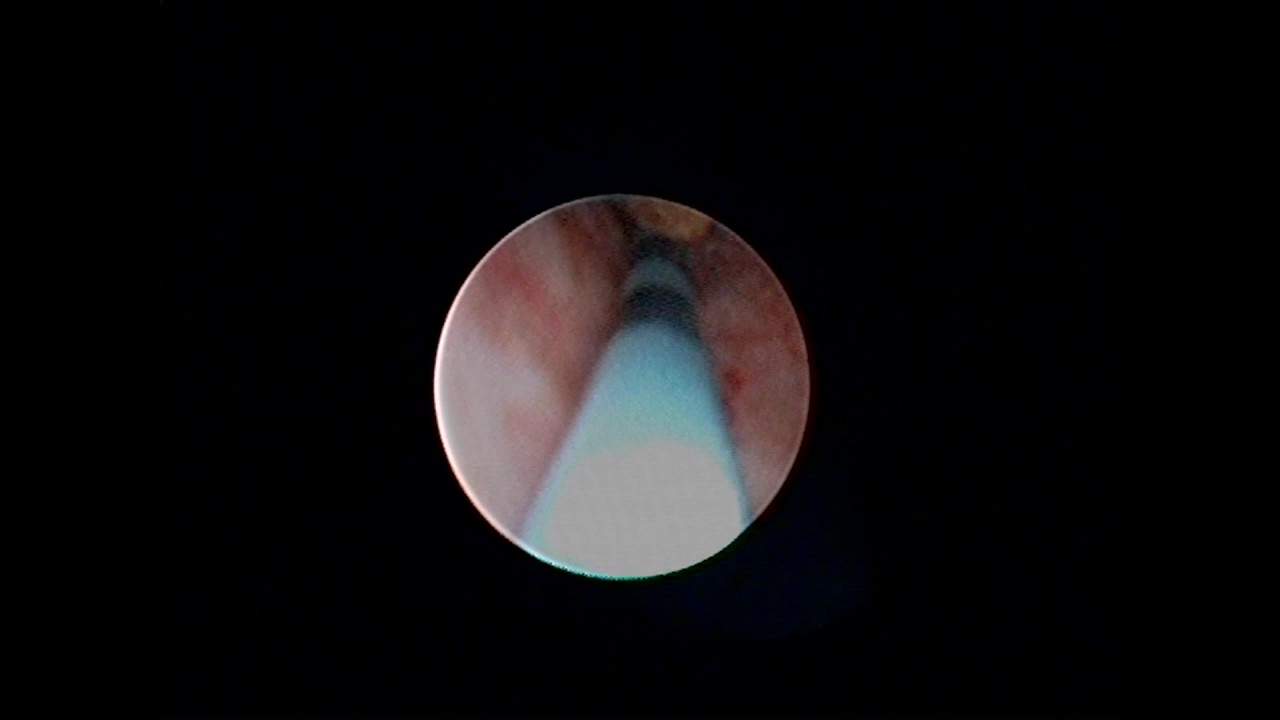

Cirugía de Próstata

Fotovaporización prostatica con laser greenlight, es una cirugia desobstructiva de la prostata que se realiza por el pene, utilizando un eqiuipo de laser verde para vaporizar el tejido prostatico que este obstruyendo la salida de la orina. Es rapido, seguro, con escaso o nulo sangrado, en algunos pacientes es un procedimiento ambulatorio y se puede realizar en pacientes con problemas cardiacos.

Prostatectomía transuretral

La cirugía de próstata a través de la uretra se llama RTUP o resección transuretral de próstata. Es una cirugía para desobstruír una próstata agrandada que causa síntomas de vaciamiento de orina, infecciones o sangrado. Puede hacerse con diferentes técnicas, las mas nuevas son las que utilizan al laser para la fotovaporización del tejido prostático (Greenlight, Tulio, Holmio) las cuales permiten una recuperación mas rápida del paciente, con escaso o nulo sangrado. La técnica tradicional de RTUP es la monopolar y su variante mas avanzada que es bipolar o de plasma son técnicas útiles y están disponibles en cualquier hospital. Se debe discutir con su medico la mejor opción para usted.